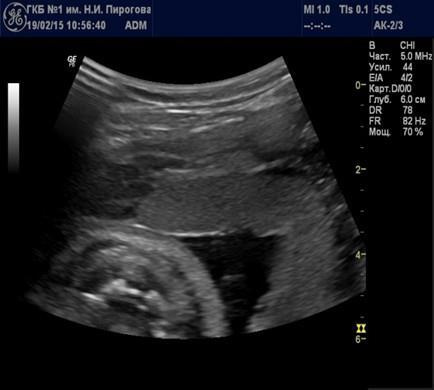

В свою очередь, эхогенность хориальной пластинки будет зависеть от угла сканирования. Наиболее высокой эхогенностью будут отличаться участки, отразившие УЗ волну под углом 90º (Рис. 6).

Рис. 6. Беременность 30 нед. Хориальная пластинка части плаценты, расположенной по передней стенке матки, при прямом (а) и косом (б) углах сканирования.